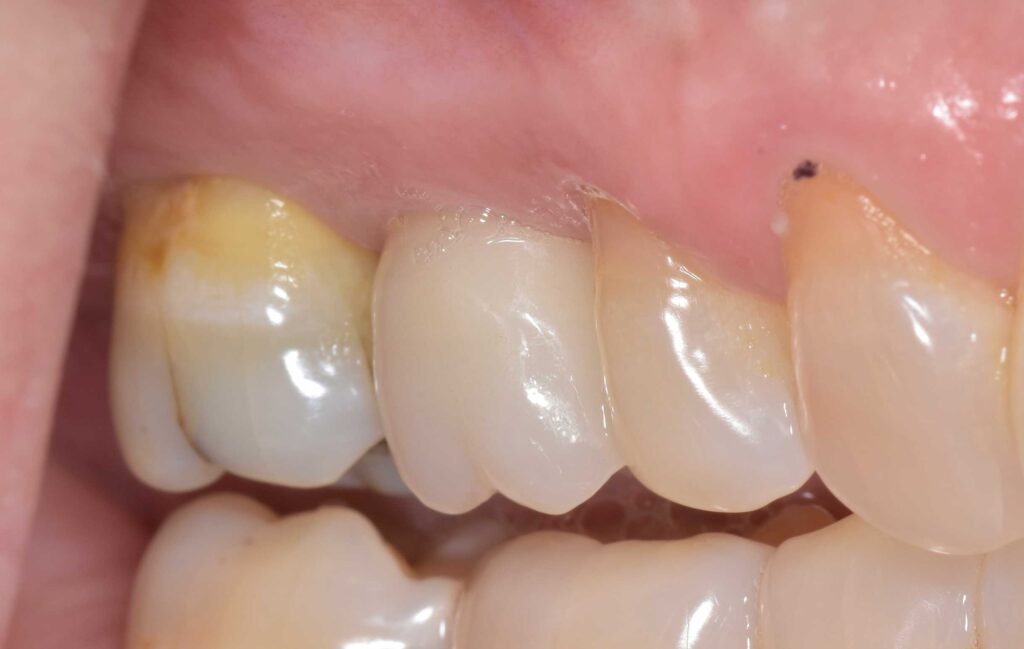

治療前

前歯部インプラント

治療後

折れてしまった歯を抜去し、周りの歯に調和したインプラント治療を行いました。